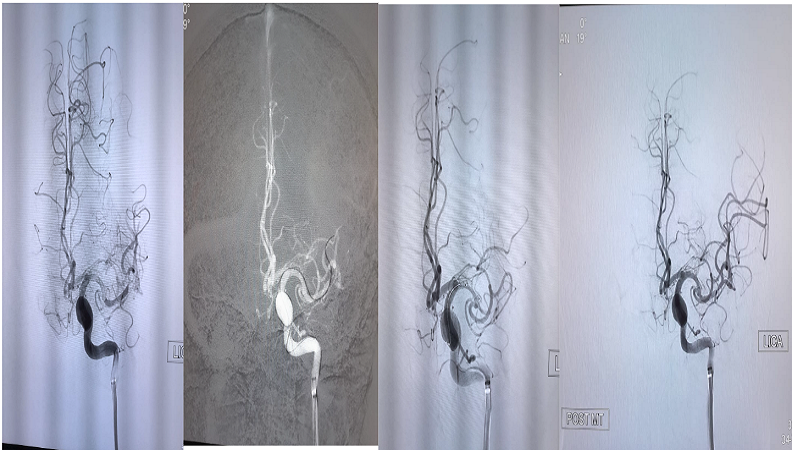

Brain Aneurysm Coiling

Brain aneurysm coiling is a minimally invasive procedure that uses tiny coils to block blood flow into an aneurysm, preventing rupture and stroke